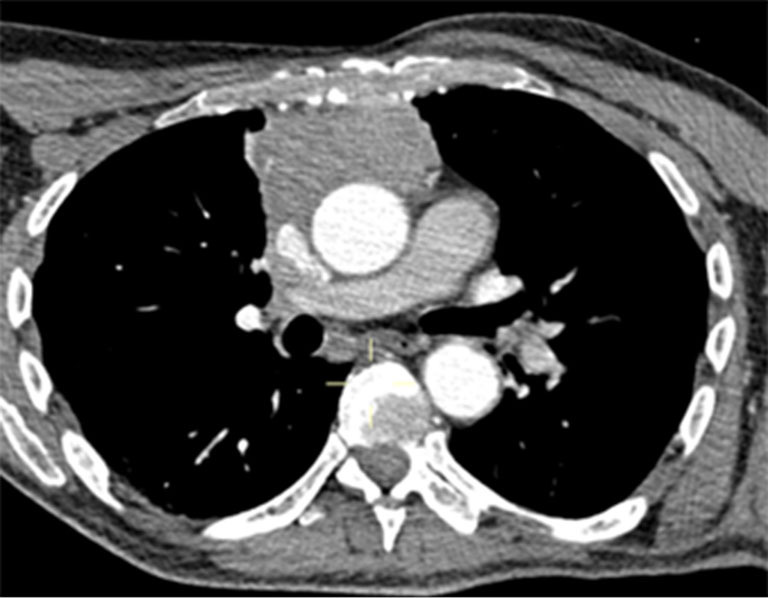

Case description: A 70-year-old patient with type-A thymoma underwent a via sternotomy thymectomy with an end-to-end caval anastomosis and an end-to-side anastomosis with the left brachiocephalic trunk by prosthesis. A 52-year-old patient with malignant peripheral nerve sheath tumor of left sternocleidomastoid muscle underwent surgical excision and chest wall reconstruction by Teflon prosthesis and pedicled flap from the rectus abdominis. A 41-year-old woman diagnosed with monophasic synovial sarcoma of the anterior mediastinum. After chemotherapy without benefit, she underwent debulking surgery with excision of this huge mass and right phrenic nerve reconstruction by neural graft from the contralateral phrenic nerve. A 23-year-old woman affected by myasthenia gravis (MG) with a type-B3 thymoma diagnosis. After chemotherapy without benefit, she underwent a thymectomy and left pneumectomy with reconstruction of the superior vena cava (SVC).